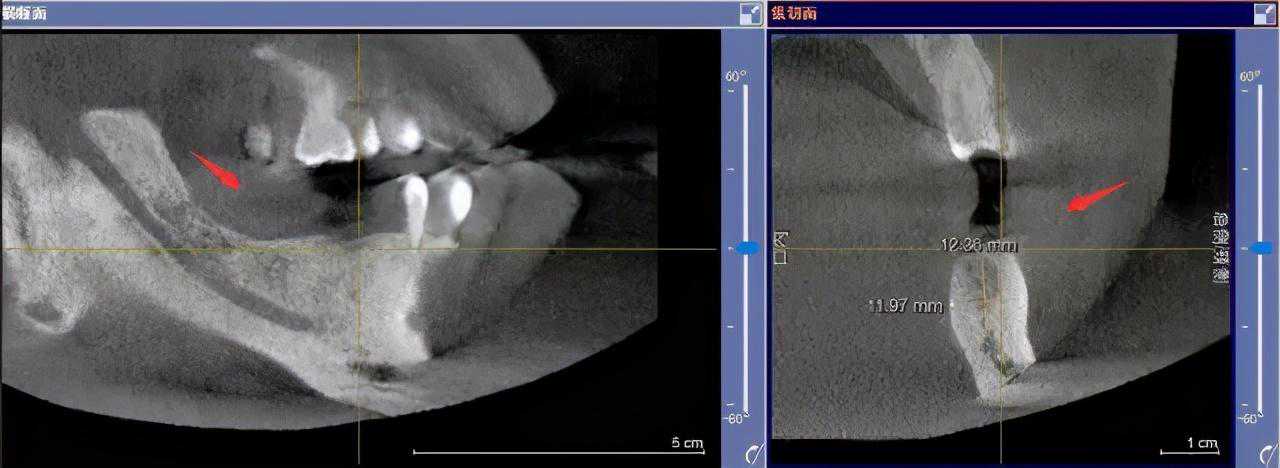

先要做一个口腔全景片、颌骨CT等

医生根据机器成像查看口腔的具体情况,

是否有炎症、牙槽骨的密度、吸收状况

以及邻牙组织、牙体组织等。

注明:此数据仅作模拟,不是确切种植数据。

如果仅靠双眼大致估测口内数据,是无法得到精准的高度、宽度的,也无法确认骨头吸收多少,是否需要植入骨粉。

对后期手术有一定的影响。

通过全景片可以“解剖”牙齿精确测量,适宜的种植角度也可确定,健康安全有保障。